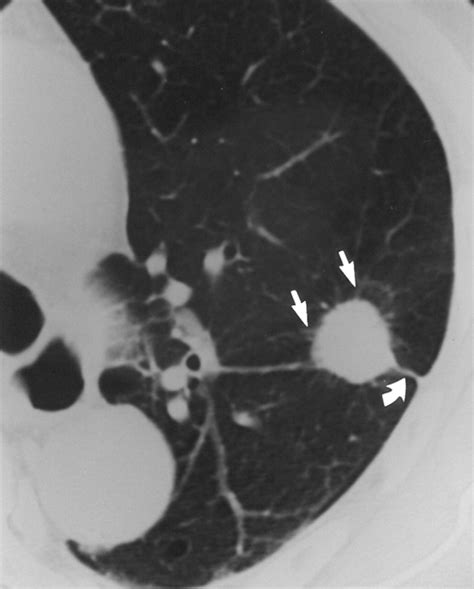

Large Cell Lung Cancer is characterized by its rapid growth and tendency to spread, or metastasize, to other parts of the body earlier than other types of NSCLC. Because these cells appear undifferentiated, pathologists often categorize this condition as a diagnosis of exclusion. This means that doctors must first rule out other types of lung cancer before confirming the diagnosis.

The cells in this type of cancer are often found in the outer regions of the lungs. Because they are peripheral, they may grow quite large before symptoms become noticeable enough to warrant a medical check-up. Recognizing the potential signs early can significantly impact the effectiveness of intervention strategies.

CT Scan Provides detailed, cross-sectional images of the lungs to assess tumor size and location.